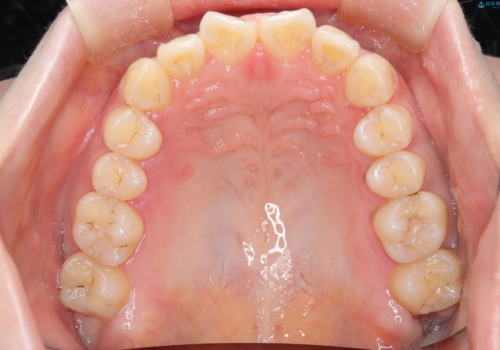

- 口元の突出感、歯のがたつきを主訴に来院された患者様です。非抜歯にて口元を下げるような治療計画を立案しました。非常に治療に対して真面目で協力的な患者様で、一緒に理想形を相談しながら治療を進めました。矯正前には、虫歯治療や親知らず抜歯を行っています。噛みしめ癖が強く、終盤は奥歯の噛み合わせのためにゴム掛けにご協力いただきました。